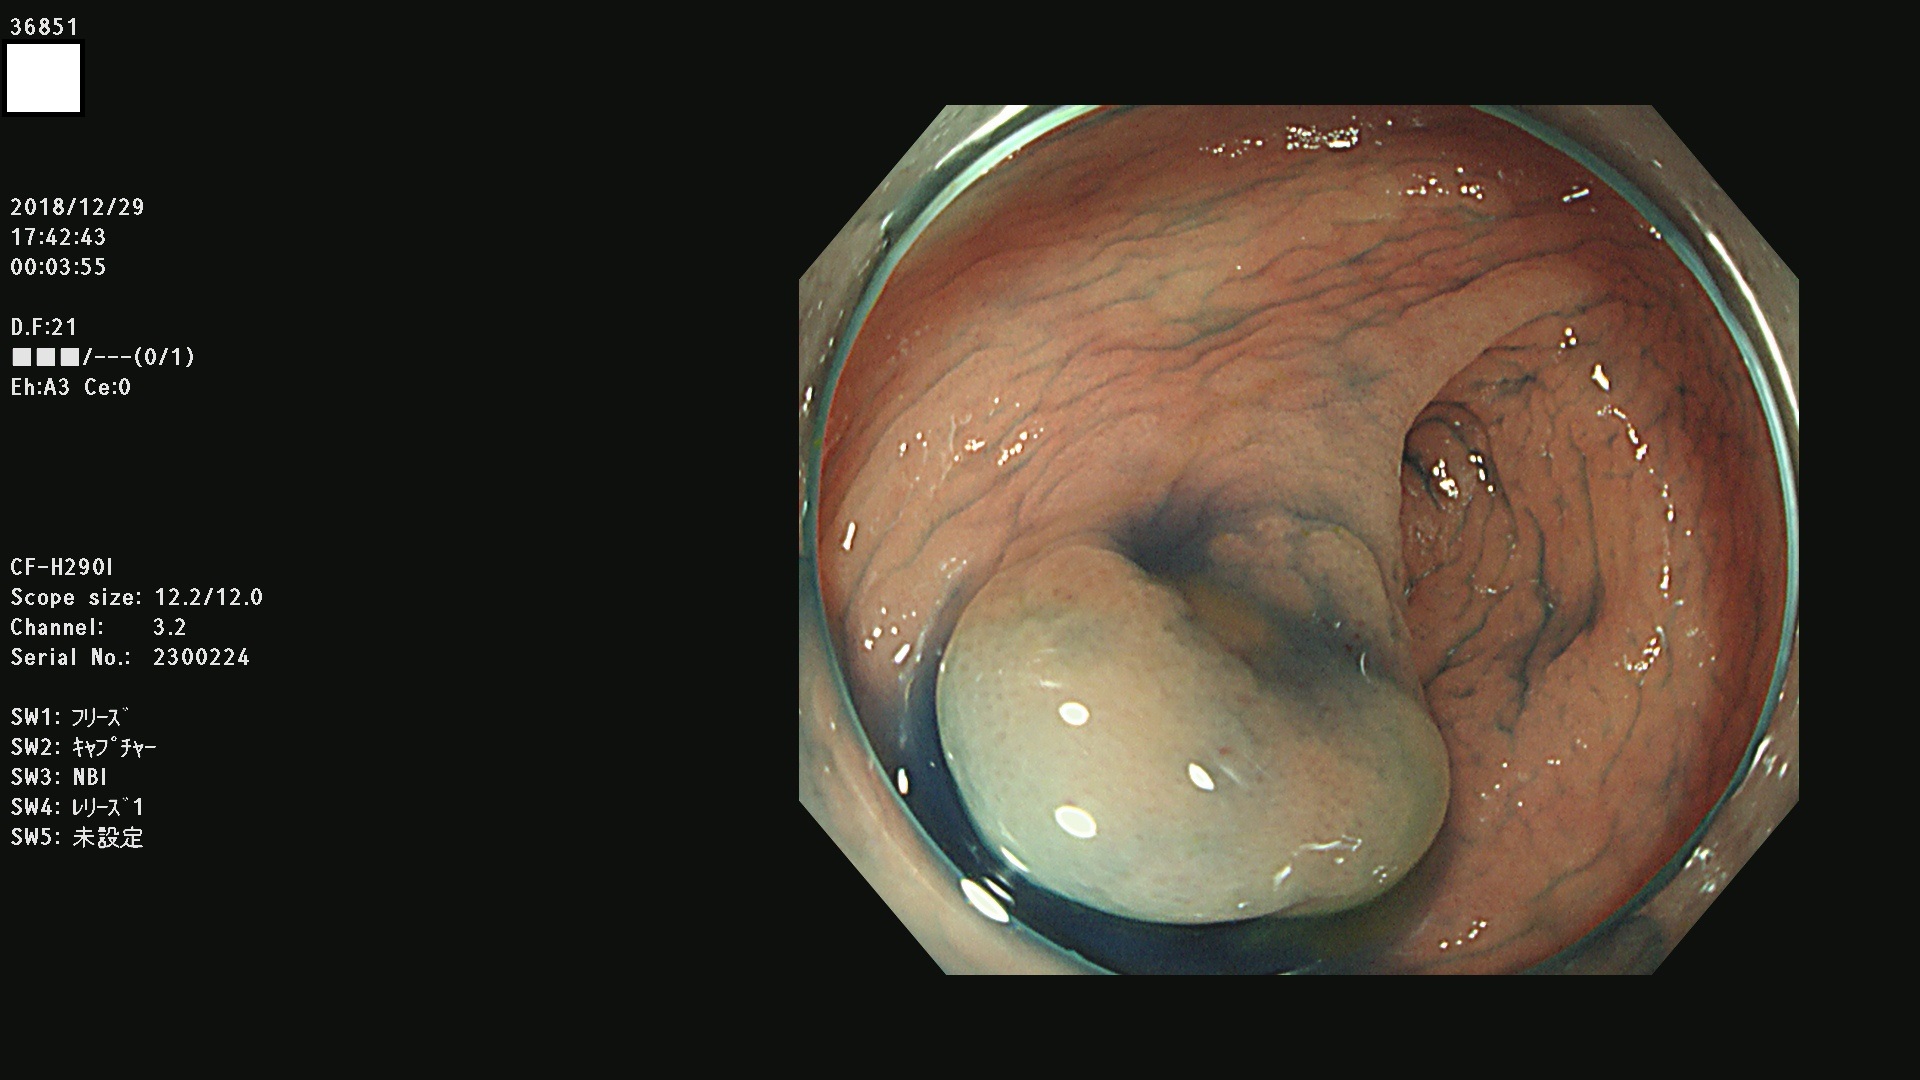

36804 36806 36807 36808 36809 36810 36811 36813 36815 36816 36817 36818 36820 36821 36822 36824 36825 36826 36828 36829 36830 36831 36832 36833 36834 36835 36837 36840 36841 36842 36845 36846 36848 36849 36851 36852 36853 36854 36855 36857 36859 36860 36861 36862(SSAPのみ) 36863 36864 36866 36868 36869 36870 36873 36875 36877 36878 36879 36881 36882 36883 36884 36885 36886 36887 36888 36889 36891 36892 36893 36894 36895 36896 36897 36898 36899

発見困難で危険性の高い平坦型病変(上記100名より抽出)